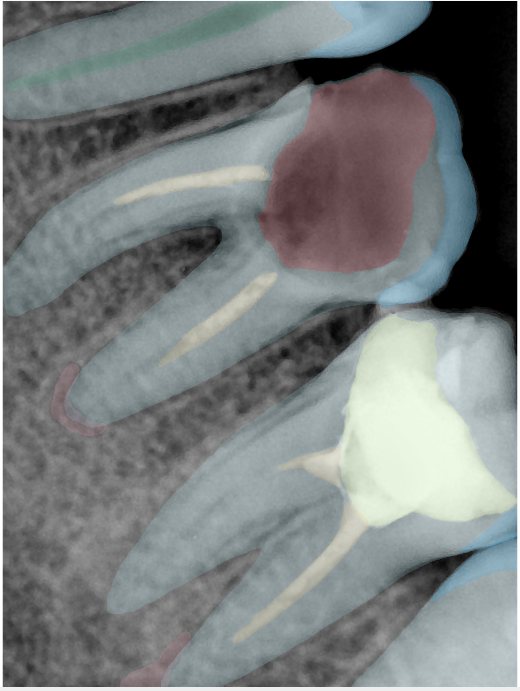

CR/DR 牙齿分割阶段记录

当前进展

- 完成了 CR/DR 牙齿相关分割训练

- 当前结果已经达到阶段预期,但仍有细节问题需要继续处理

相关测试

遇到的问题

- 训练过程中出现过 mask 下移问题

- 部分结果会出现 box 填充异常

- mask 边缘仍然有比较明显的锯齿感

第二版算法问题测试

| 第一版 | 第二版 | 是否解决 | |

|---|---|---|---|

![]() | ![]() ![]() 边角识别有问题 龋齿识别不全 牙髓识别不全 | ![]() | 解决 |

![]() | ![]() 边角识别有问题 识别信息有误 自查(牙冠识别不全) | ![]() | 解决 |

![]() | ![]() ![]() 边角识别有误 大范围填充识别遗漏 | ![]() | 解决 |

![]() | ![]() 识别信息不全 | ![]() | 解决 |

![]() | ![]() ![]() 边角问题 牙胶识别不全 牙冠识别不全 | ![]() | 解决 |

![]() 换图片 | ![]() | ![]() 牙冠部分稍微白了一些就识别成小范围修补,部分判断异常 | 部分解决,修复类略敏感,牙冠部分稍微白了一些就识别成小范围修补,部分判断异常。 |

![]() | ![]() ![]() 牙冠识别不全 牙髓不全 根尖炎龋齿识别有误 | ![]() | 解决 |

![]() | ![]() | ![]() | 解决 |

![]() 换图片 | ![]() | ![]() | 解决 |

![]() | ![]() 牙冠识别有误 | ![]() | 解决 |

![]() 换图片 | ![]() ![]() 边角识别有误 | ![]() 修复类敏感 | 部分解决,图像过白,导致修复类判断异常。 |

![]() 换图片 | ![]() 牙冠识别不全 | ![]() 修复类敏感 | 部分解决,图像过白,导致修复类判断异常 |

结论:修复类出现了不鲁棒的情况,后续需要加入轮廓的扩充数据进行增强。